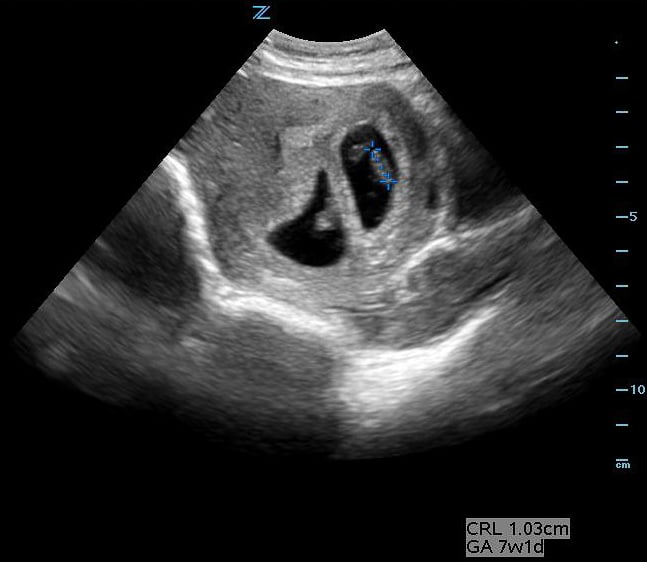

Obstetrics

- Obstetric ultrasound (OB US) performed by emergency clinicians in many resource-rich environments is often limited to the confirmation of an intra-uterine pregnancy, dating, fetal heart tones, and movement for well-being.

- This paradigm is predicated on a mother having relatively close follow-up with OB/GYN, recurrent imaging, and planned delivery in a hospital.

- Both obstetric textbooks20 and a recent large international randomized controlled trial (RCT) 21 describe a relatively simple second or third trimester OB US protocol assessing risk of maternal or fetal complication and need for referral to and delivery at advanced healthcare facilities in RLS.